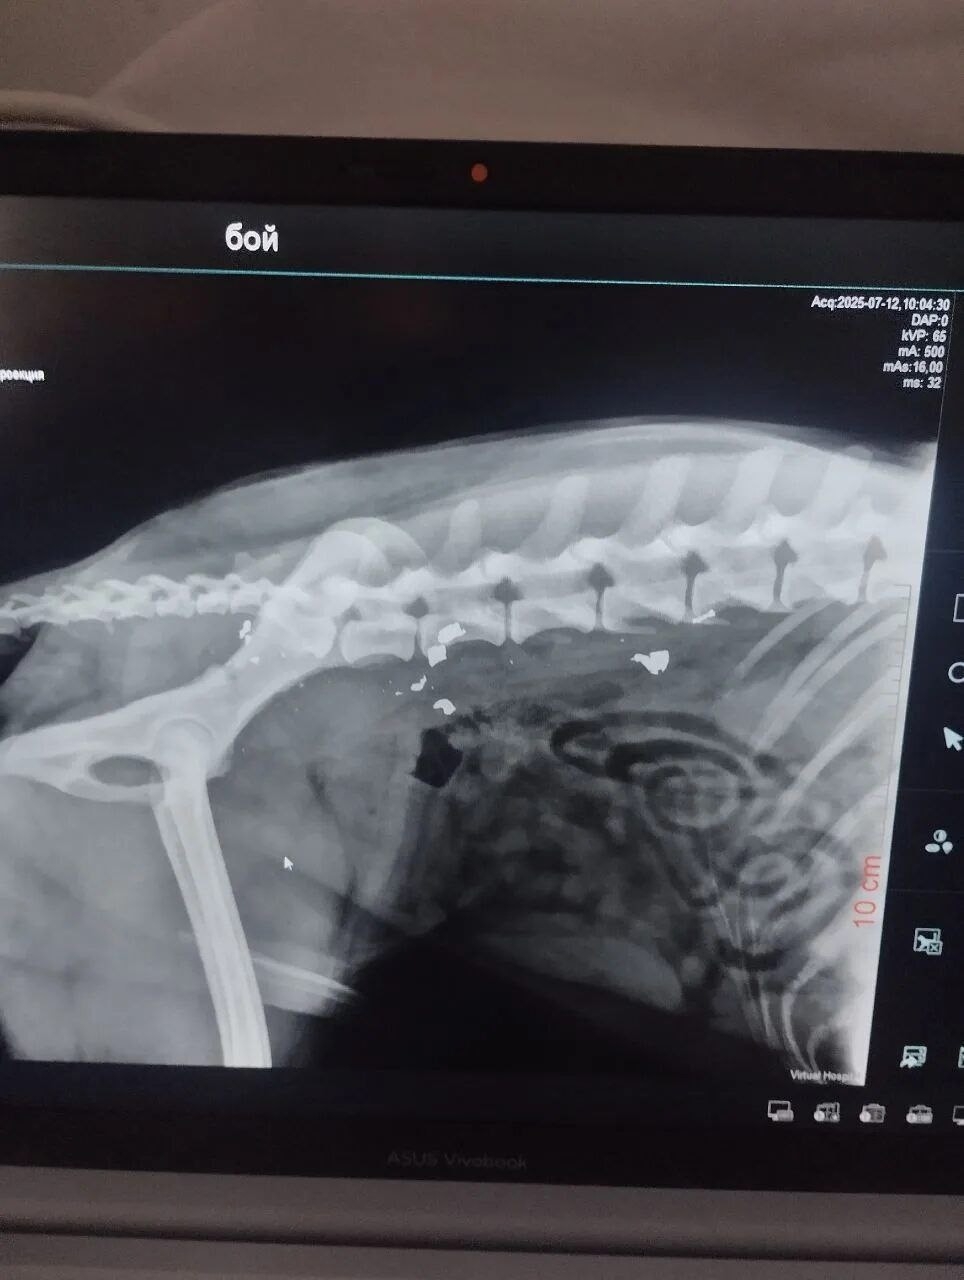

Бой — невероятно добрый и ранимый пес, но сейчас его жизнь превратилась в ад. Фото и видео были сделаны осенью, а сейчас ситуация катастрофическая: лапа распухла в разы, началась гангрена. Соседи говорят, что пес совсем плох — если не забрать его из этого гиблого места прямо сейчас, он умрет от сепсиса.

Когда-то Боя уже возили в Волгоград на рентген, но полноценного лечения он не получил и снова оказался на улице. Итог — инвалидность и гниющая заживо конечность.